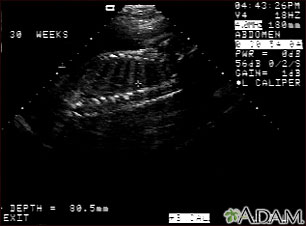

Ultrasonido de un feto normal; columna y costillas

Ultrasonido normal a las 30 semanas de gestación. En el centro de la pantalla se observa el perfil nítido de la columna vertebral y las costillas. La cruz se encuentra ubicada entre dos costillas justo por debajo de la columna vertebral.